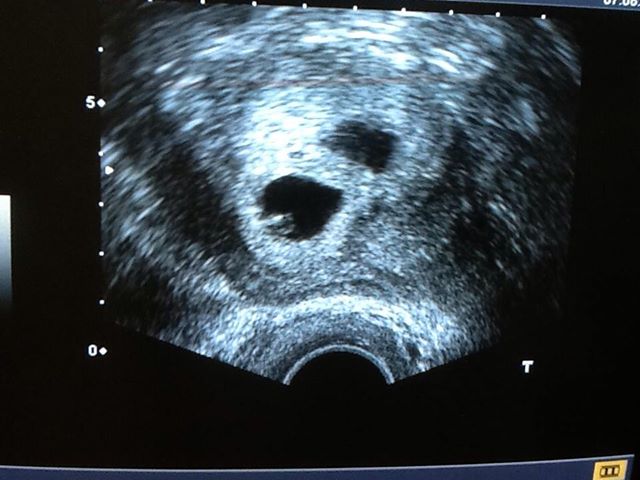

婦女子宮內膜異位症 像顆大草莓--台灣導報

婦人罕見外陰長草莓 醫師﹔子宮內膜異位瘤